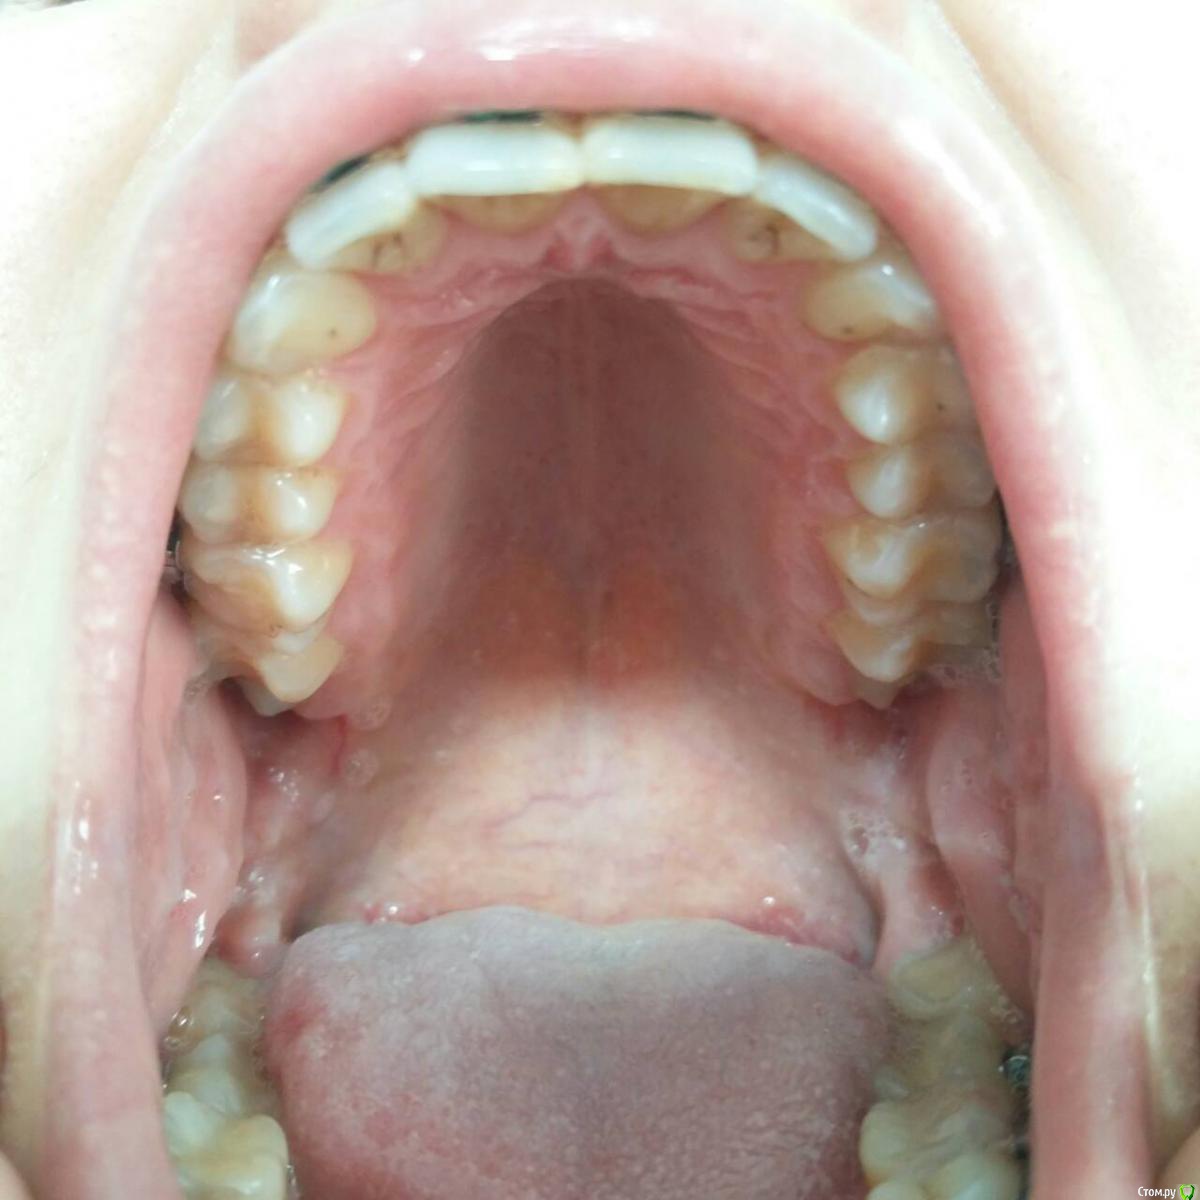

Валг Опубликовано 31 августа, 2018 Поделиться Опубликовано 31 августа, 2018 Добрый день!Нужен совет по поводу исправления прикуса, перекрестный, 3 класс, но точно я не уверена, врач мне мало что разъяснил. Ношу уже 4 месяца, и теперь врач мне говорит что нужно удалять нижние 5, так как они мешают смыканию челюстей и зубы вынуждены сильно наклонятся вперёд.Изначально ортодонт говорил, что удаление зубов не потребуется. Посоветуйте, пожалуйста, что делать! Ссылка на комментарий

Валг Опубликовано 31 августа, 2018 Автор Поделиться Опубликовано 31 августа, 2018 Мои фотографии Ссылка на комментарий

Kazankov.Egor Опубликовано 1 сентября, 2018 Поделиться Опубликовано 1 сентября, 2018 Как минимум, я бы сейчас остановился: смущает то, что на ОПТГ (снимок всех зубов) центры зубных рядов более-менее совпадают, скорее всего это проблема зубных контактов, которые имеются на данный момент. Первое - депрограммирование челюсти. По остальному: нужно видеть фото полные внутриротовые и модели "до" и "на этапе". Ссылка на комментарий